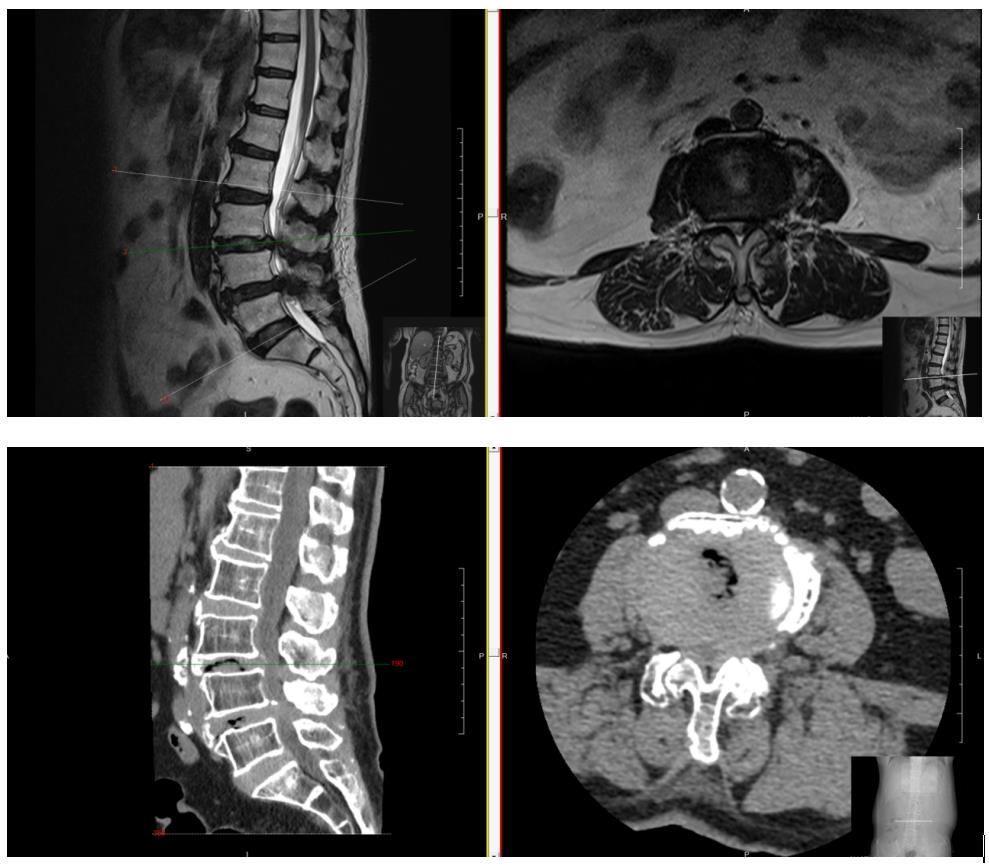

▲患者术前影像学资料

女性患者陈大妈61岁,因“腰痛伴双下肢麻痛5年。”入院。曾辗转区内外多家医院求医,诊断为“1、腰椎管狭窄症;2、腰椎滑脱症”,经过反复保守治疗,但是效果不佳,严重影响日常生活。我院脊柱微创科王义生主任专家团队通过会诊,一致认为可进行手术治疗。本着“微创化”的治疗理念,结合患者实际需求,制定了详细有效的手术治疗方案。在与患者及家属充分沟通后,决定为患者实施OSE (Open Spinal Endoscopy, Openscopy)-单孔双入路脊柱内镜(开放式脊柱内镜,分体式脊柱内镜)术。